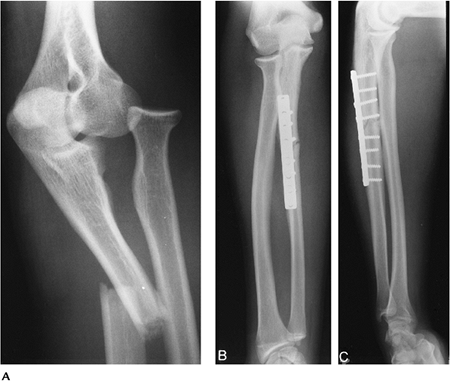

P.531

![]() |

FIGURE 8-14 Monteggia fracture. (A) Oblique radiograph showing an anterior dislocation of the radial head with a proximal ulnar fracture. Postreduction AP (B) and lateral (C) radiographs with internal fixation of the ulnar fracture.